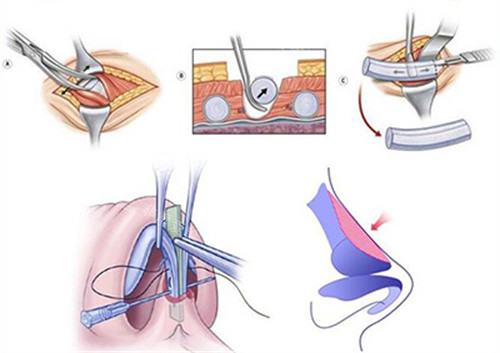

头一点是“快速小切口取肋法”。

一听要取肋骨,很多人头一反应就是害怕,觉得伤口大、疼得出色。

但朴院长的技术可以将取肋切口控制在仅1.1厘米左右。

整个取肋过程只需要25到40分钟。

这种精细操作大大减少了组织的创伤,术后的疼痛感自然会减轻很多。

修复的比较快,患者的舒适度提升不是一点半点。

第二点是“双线缝合稳定技术”。

鼻子做完不仅要好看,更要持久稳定。

这项技术通过特殊的缝合方式,能有效增强鼻内部支架的稳定性。

目的是为了更大程度地避免术后可能发生的鼻头挛缩、变形等问题。

让做好的鼻型能够长久地保持住。

第三点是“筋膜包裹技术”。

这是对抗肋骨软骨吸收的一大利器。

朴院长在取肋软骨时,会创新性地保留一部分肋骨表面的筋膜。

然后在雕刻好软骨支架后,用这层自体筋膜把它包裹起来。

这样做能显著降低软骨移植后被身体吸收的比率。

确保术后鼻子的形态和高度能够长期维持,不会因为吸收而慢慢变矮。

第四点就是“疤痕隐形处理”。

无论是取肋的微小切口,还是鼻内的切口。

他都采用内外双层的精细缝合方式。

目的就是为了让疤痕愈合后尽可能不明显。

真正做到在改善容貌的同时,兼顾了“无痕”的美观要求。

这些技术细节叠加在一起,共同支持了更终结果的“自然”与“稳固”。

也是为什么他的直鼻术例能那么好看、那么惊艳的底层逻辑。